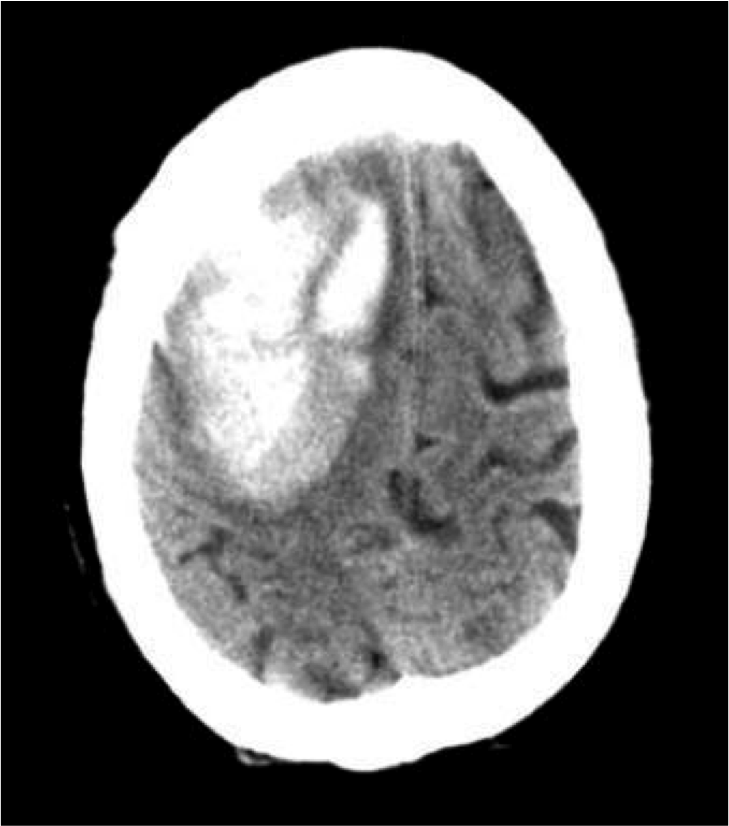

what is shown

Intraparenchymal hemorrhage